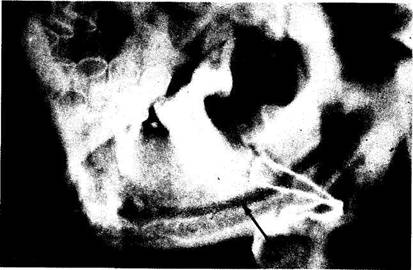

Нередкое возникновение остеомиелита нижней челюсти в области ее угла, с нашей точки зрения, обусловлено не только преимущественным поражением кариесом и его осложнениями больших коренных зубов, но и более частым образованием при подобной локализации перелома нагноившихся гематом, а также неудовлетворительной фиксацией малого фрагмента нижней челюсти при консервативно-ортопедическом лечении. Поэтому при такой ситуации мы отдаем предпочтение хирургическим методам лечения (рис. 62).

На рентгенограммах определяется перелом нижней челюсти в области угла, большой фрагмент нижней челюсти репониро-ван и фиксирован назубными шинами, малый фрагмент резко смещен вверх. При таком смещении отломка челюсти происходит анатомический перерыв нижнего альвеолярного нерва, что приводит к нарушению трофики тканей в зоне повреждения и способствует возникновению травматического остеомиелита.

Рис. 62. Перелом нижней челюсти в области угла. Резкое смещение отломков, приводящее к анатомическому перерыву нижнего альвеолярного сосудисто-нервного пучка: а) до лечения (рентгенограмма); б) произведено репонирование и фиксация фрагментов нижней челюсти проволочным швом (рентгенограмма). Пояснение в тексте ( стр. 121).